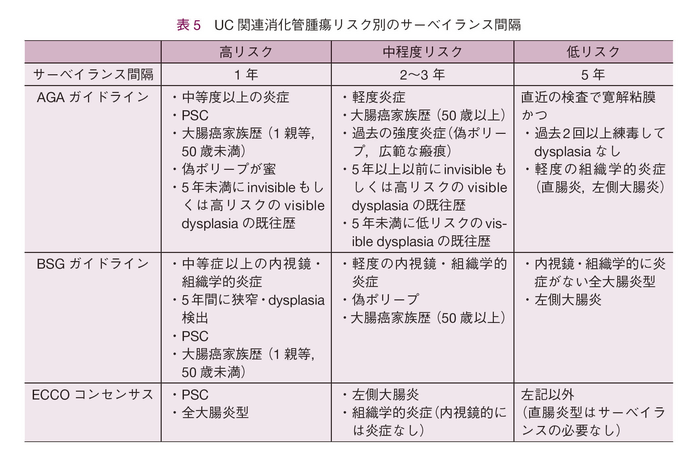

サーベイランスの対象を考慮するうえで,リスク因子を把握することは重要である。通常の大腸癌のリスク因子は加齢,男性,家族歴,肥満,喫煙,赤身の肉(read meat)摂取などであるが,UC関連大腸腫瘍のリスク因子としては,PSC,全大腸炎型,長期経過例,内視鏡的・組織学的炎症の持続などが挙げられている8)。本邦では難病申請の更新時の書類作成のために大腸内視鏡検査を行う傾向があったため,リスクにかかわらず毎年検査を施行する場合も少なからずあるが,海外のガイドラインでは,リスク因子別にサーベイランスの施行間隔が記載されている(表5)。

高リスク群としては活動性の強い全大腸炎型,50歳以下の大腸癌の家族歴がある場合,PSC,5年以内にdysplasia(HGD or LGD)の検出の既往が挙げられており,これらのリスクがある場合にはサーベイランスを毎年行うことが推奨されている。中程度リスク(Intermediate)群としては,50歳以下の大腸癌の家族歴がある場合,軽度の内視鏡的・組織学的炎症の持続などが挙げられており,2~3年ごとのサーベイランスが推奨されている。低リスク群は5年おきのサーベイランスが推奨されており,内視鏡的・組織学的炎症のない全大腸炎型や左側大腸炎型5),2回以上dysplasiaがないもしくは組織学的活動性がなく,かつ直近の検査で内視鏡的寛解が確認されている場合をあげている4)。また内視鏡所見からみた大腸癌発症のリスク因子についても研究がなされており,内視鏡的寛解例は発症のリスクを低下させること,一方で炎症性ポリープ,管腔の狭小化はリスクを増加することが報告されており9),慢性に炎症が持続すること,過去に強度の炎症を有することにより炎症を母地とした発癌のリスクが高まると考えられている。